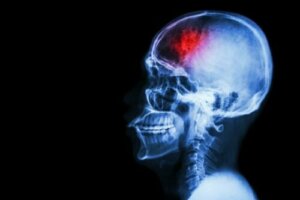

Udar pojawia się, gdy do danego obszaru mózgu dopływa niewystarczająca ilość krwi lub dochodzi do jej odcięcia. W związku z tym może dojść do uszkodzenia tego organu, a nawet śmierci pacjenta. Aby tego uniknąć, powinnaś dowiedzieć się jak możesz chronić się przed udarem mózgu.

Udar mózgu to choroba naczyniowo-mózgowa, która dotyka naczyń krwionośnych dostarczających krew do mózgu. Rozwija się, gdy naczynie krwionośne pęknie lub zostanie zablokowane przez skrzep lub inną cząsteczkę.

Jeden z artykułów opublikowanych w MSD Manual wyjaśnia, że takie pęknięcie lub zablokowanie prowadzi do przerwania dostarczania do danej części mózgu krwi, tlenu i glukozy, które są niezbędne do jego funkcjonowania. W konsekwencji komórki nerwowe w części mózgu dotkniętej udarem nie otrzymują żadnego tlenu. Tym samym nie są w stanie funkcjonować i w kilka minut umierają.